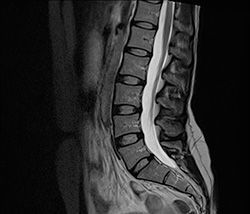

МРТ позвоночника

<p>Среди современных диагностических исследований позвоночника, проводимых при помощи сложного оборудования, одно из ведущих мест занимает МРТ, или магнитно-резонансная томография. По информативности и безвредности для организма МРТ позвоночника намного превосходит не только обычную рентгеноскопию, но подчас и компьютерную томографию, позволяя практически со стопроцентной достоверностью диагностировать подавляющее число заболеваний и патологий позвоночного столба, а также прилегающих к нему тканей.</p>

<p>Принцип томографического исследования на основе магнитного резонанса ядер атомов водорода был открыт в 1973 году профессором В.А.Ивановым. Сегодня уже не возникает вопроса, где сделать МРТ позвоночника в Москве – установки имеются во многих клиниках и медицинских центрах, в том числе и многопрофильной клинике ЦЭЛТ (здесь установлен высокопольный томограф с индукцией магнитного поля 1.5 Тл). С помощью томографа делают тонкие, до 1 мм, срезы анатомических подробностей позвоночника, на основе которых затем создается его трехмерное изображение.</p>

<p>Заболевания опорно-двигательного аппарата нередко бывают сложными для диагностики обычными методами. Возможность сделать МРТ позвоночника позволяет избежать малоприятных, а зачастую и опасных инвазивных исследований, так как дает возможность врачу своими глазами увидеть состояние позвонков, межпозвонковых хрящей и мягких тканей пациента.</p>

<p>Поводом для назначения МРТ служат нарушения деятельности опорно-двигательного аппарата, болевые ощущения различной локализации и другие симптомы. Как правило, врач назначает исследование не всего позвоночника, а только интересующего его отдела – МРТ шейного отдела позвоночника, МРТ грудного отдела позвоночника, МРТ пояснично-крестцового отдела позвоночника или нескольких отделов одновременно.</p>